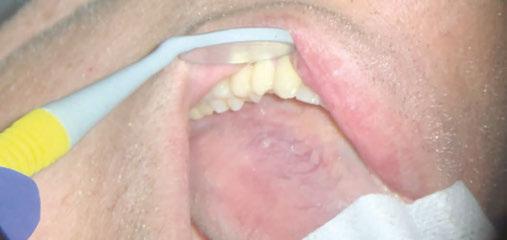

Figure 3: Intraoral vestibule exam

Intraoral exam

Thorough inspection of the lips, buccal mucosa, gingiva, hard/soft palate, tongue (dorsal, lateral, and ventral), and oropharynx. Use gauze to pull and manipulate the tongue for complete visualization (Figures 3-4).